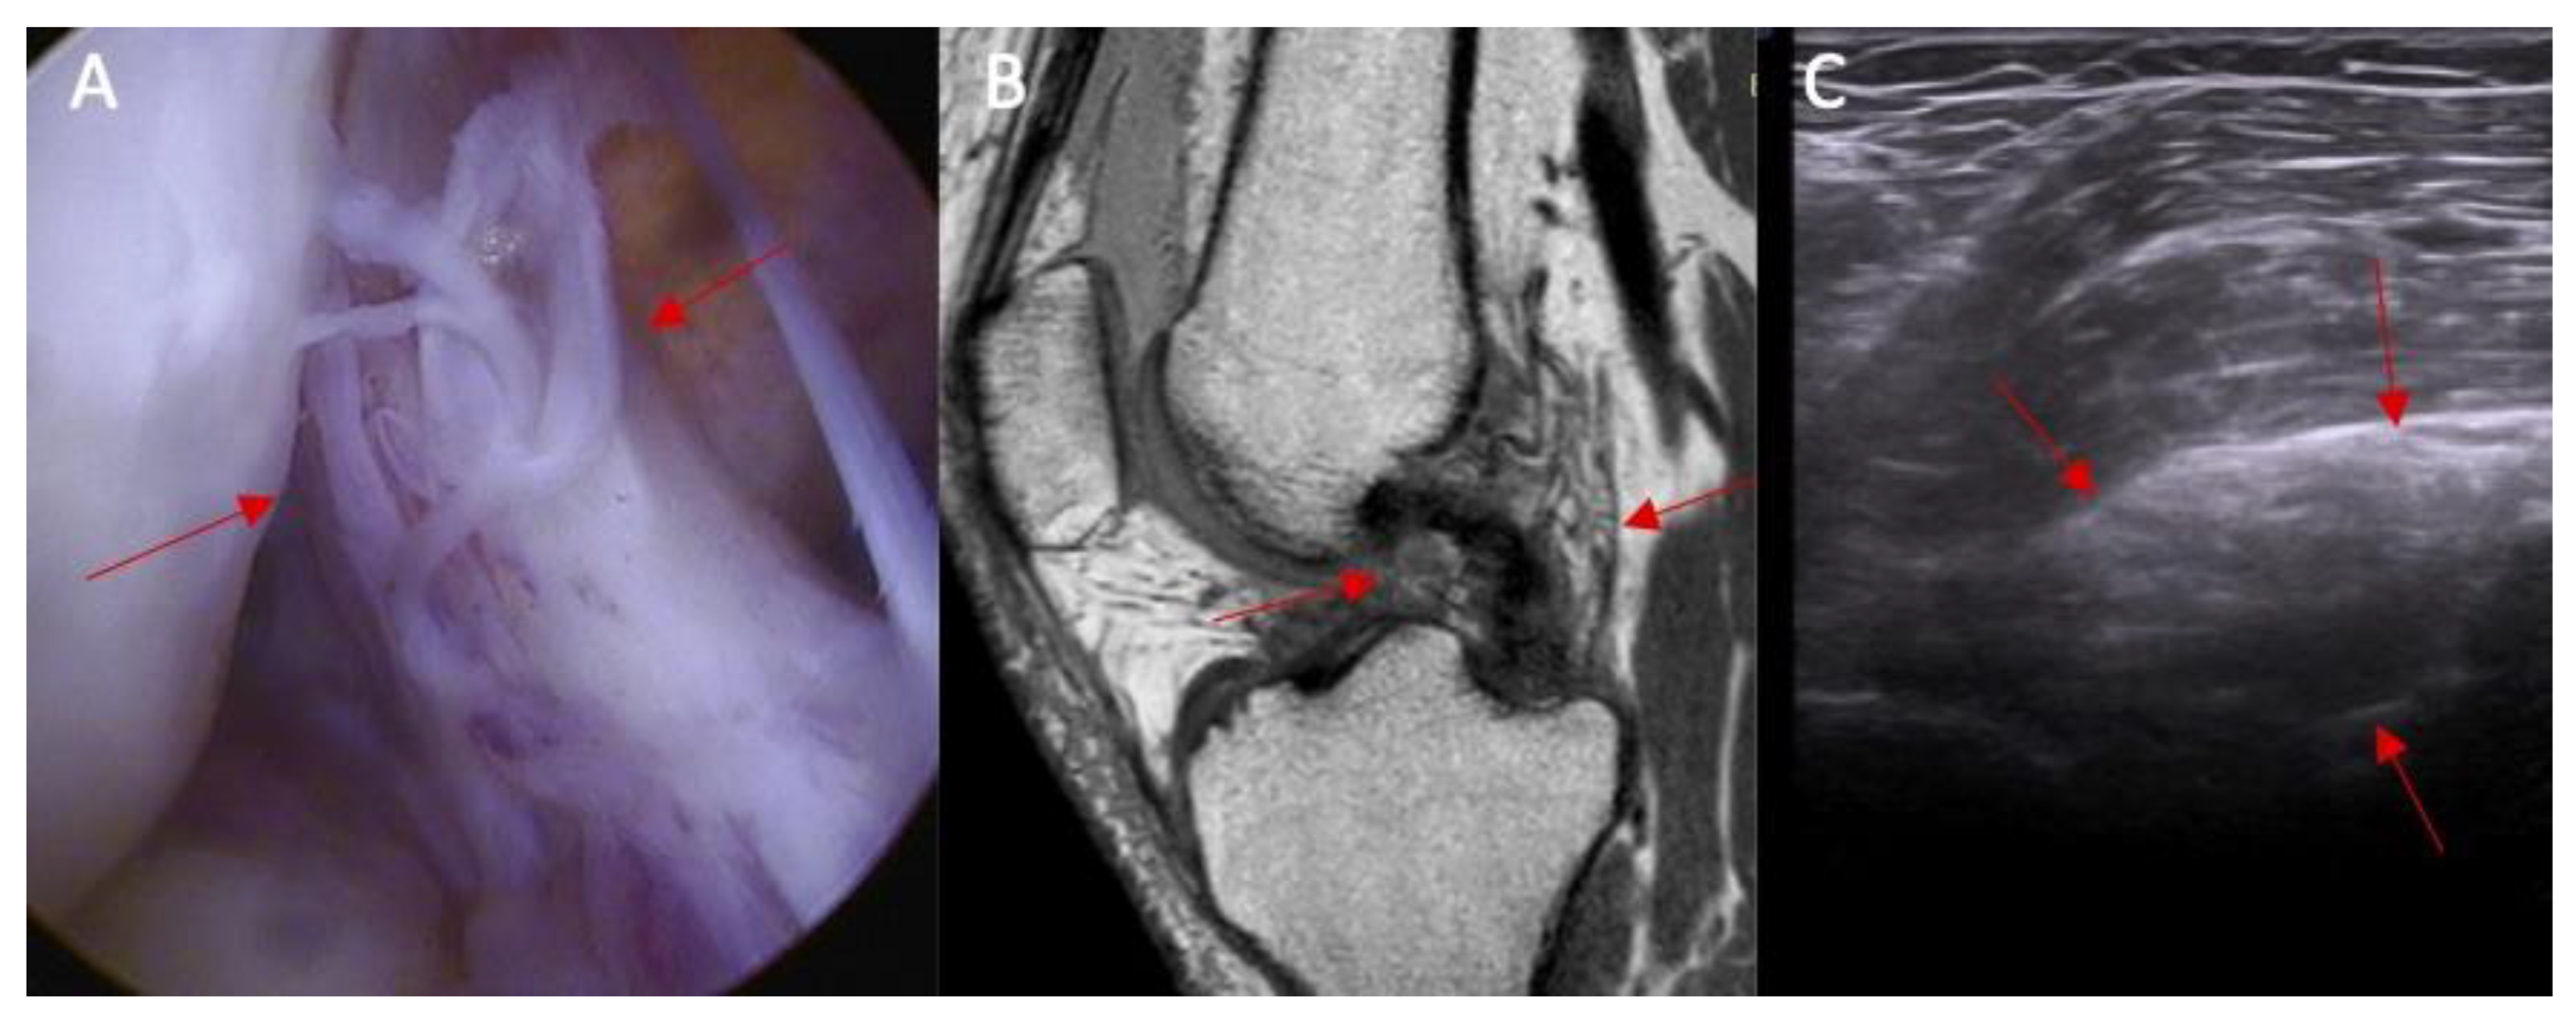

- Swelling/scarifications of the ACL proximal attached to lateral femoral condyle—the patient is in prone position with knee full extension. The transducer is applied transversely to long axis of the lower limb in popliteal fossa.

- Swelling/scarifications of the ACL/posterior crucial ligament (PCL) with change of the morphology of the posterior joint capsule complex—the patient is in prone position with knee full extension. The transducer is applied parallel to the long axis of the lower limb.

3.1. Part I—Anatomical Study

3.2. Part II Clinical Study